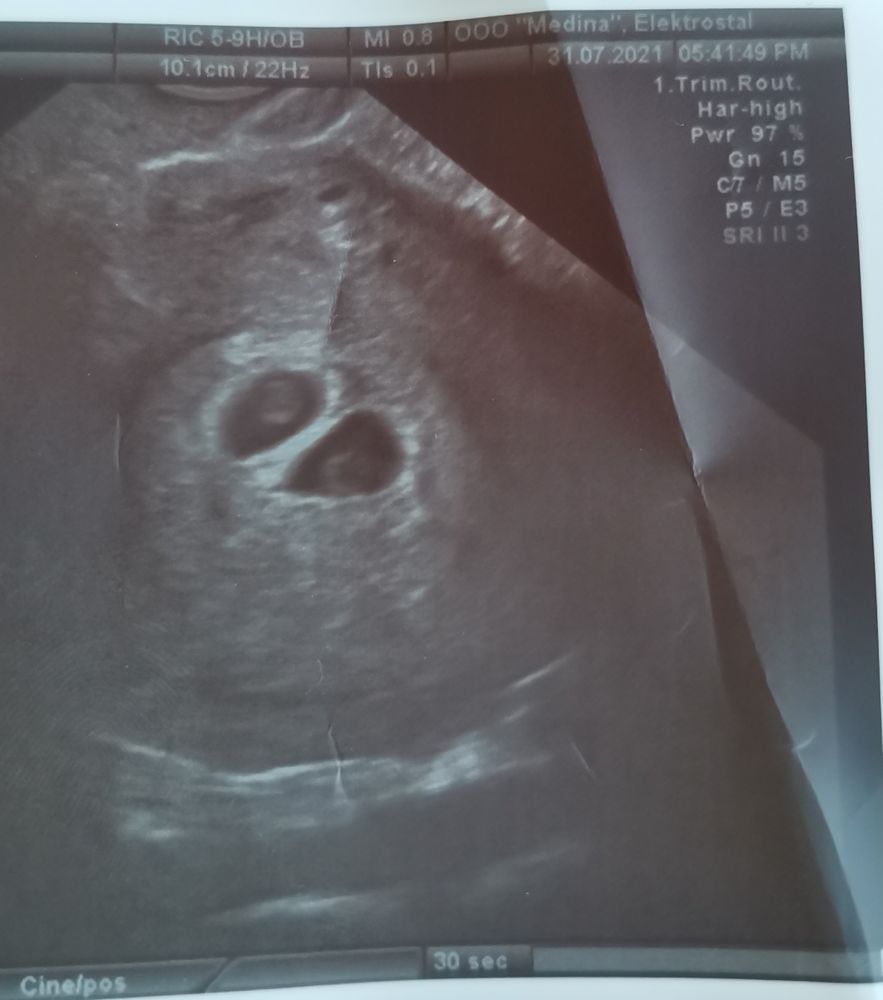

Мои поздравления! Мне всегда казалось почему то, что у вас двойня)) видимо знак)) Обязательно вступайте в наши сообы- многоплодная беременность и двойняшки. родившие девочки все консультируют, рассказывают, очень много полезной информации там найдёте 🙌🏻 все таки многоплодка это особый случай:) У меня была моно ди двойня, соответственно близнецы. вот я не поленилась и нашла первое узи - действительно не отличишь от ди ди, это прояснится уже позже.  Изображение сразу по всему напишу: про хгч: у меня был низкий. Вот прям низкий и рос плохо, и ничего это не означало. про токсикоз: у меня был птздц😗, очень плохо мне было. И долго. Было плохо очень долго..) мне как-то сказала врач, что если в предыдущие б был токс, то скорее всего повторно будет, это особенность организма, а не беременности. про ицн: очень, очень и очень плохая предыстория для двойни. Конечно с шейки вам глаз не спускать придётся.. опять же, по словам врача, это тоже особенность организма. Но двойня это фактор, который повышает вероятность ицн для любого организма, поэтому… скорее всего ицн повторится, надо просто вовремя принять меры. насчет переживаний: двойня это крайне непредсказуемая история… может не развиваться, может замереть, может отставать. Может понадобится экс, может быть ер, могут пересидеть и получится перерастяжение матки, а могут родиться преждевременно и кстати вероятность очень высока, учитывая ицн. Вы извините, что это все говорю, но вы девушка умная и должны понять. чем скорее вы эти риски примите как данность, тем вам будет лучше. Иначе от узи до узи будете сходить с ума) а от всего остального вообще никто не застрахован. так что не бойтесь, все вопросы решите по мере поступления. Главное, отдайтесь лучшим врачам, я настоятельно рекомендую Кулакова, Кирилл Витальевич Костюков узи эксперт по двойням, не пожалейте денег наблюдаться у него. Врачи все хорошие, я была у Гладковой, многие девочки у Тетруашвили, у Грачевой и других, спокойно выбирайте. Удачи!!! 🍀

Елена, да, возможно, хотя в заключении узи пока пишут диди, но, я так поняла, что от моноди ее сейчас не отличить) мама моей подруги, акушера-гинеколог, тоже считает, эьо это близнецы) Спасибо!) будем стараться помочь малышам дорасти до срока и появиться на свет здоровыми и счастливыми✊